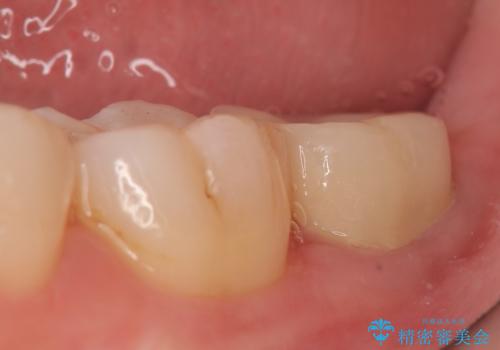

- 左下の一番奥の歯が時折激しく痛むので診て欲しいといらっしゃった方の症例です。以前に他院を受診したところ、そもそも被せ物を入れるスペースがないため抜歯しかないと言われたとのことでした。

診査の結果根尖病変を認めたため再根管治療を行った後に、被せ物を入れるスペースを作るため歯冠延長術を行いました。

歯冠延長術について

歯冠長延長術とは歯肉弁根尖側移動術とも言い、歯の高さが低くクラウン(被せ物)による治療が難しい場合に、歯茎を歯根方向に下げることで歯の高さを確保する手術です。歯の高さが十分にあることで、外れにくいしっかりとしたクラウンを被せることができます。